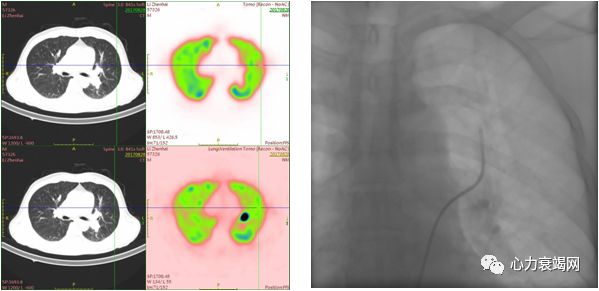

左肺下叶背段、右肺上叶前段、右肺下叶背段、右肺下叶基底段及右肺下叶外基底段通气/灌注显像不匹配

肺通气/灌注扫描:左肺上叶及下叶、右肺上叶、中叶及下叶肺栓塞高度可能

2017-06-27右肺动脉A5血管扩张术前后对比

右肺中叶外侧段、内外基底段、左肺上叶舌段、下叶内基底段灌注明显改善